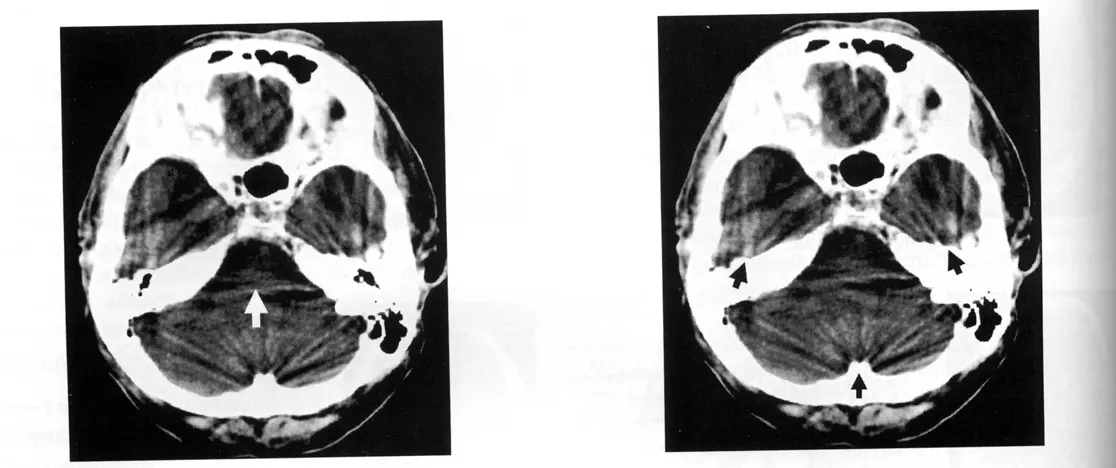

D1. Beam hardening artifacts

Beam hardening은 CT artifact로, X-ray beam이 환자를 통과하면서 lower-energy X-rays가 더 쉽게 흡수되어 평균 에너지가 증가하면서 "harder"해지는 것이 원인입니다. 이는 부정확한 image data로 이어지며, dense structures(뼈 같은) 사이의 dark streaks, 물체의 dark center("cupping"), metal implants 주변의 dark halo 또는 "blooming"으로 나타날 수 있습니다. 이 artifact는 beam의 초기 에너지를 증가시키거나, pre-hardening filters를 사용하거나, iterative reconstruction algorithms를 사용하거나, dual-energy CT techniques를 사용하여 해결됩니다.

왼쪽그림 화살표: brain stem부분이 시커멓게 보인다.

오른쪽그림 화살표 : 검은 줄무늬무늬로 artifact가 보인다